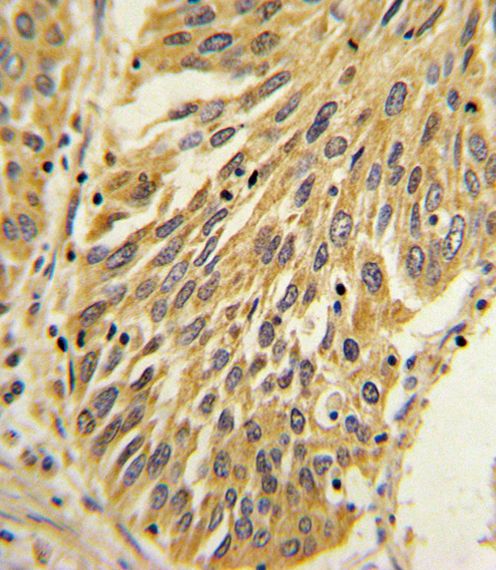

This IL1B antibody is generated from rabbits immunized with a KLH conjugated synthetic peptide between 148-174 amino acids of human IL1B.

IHC-P: 1:10~50